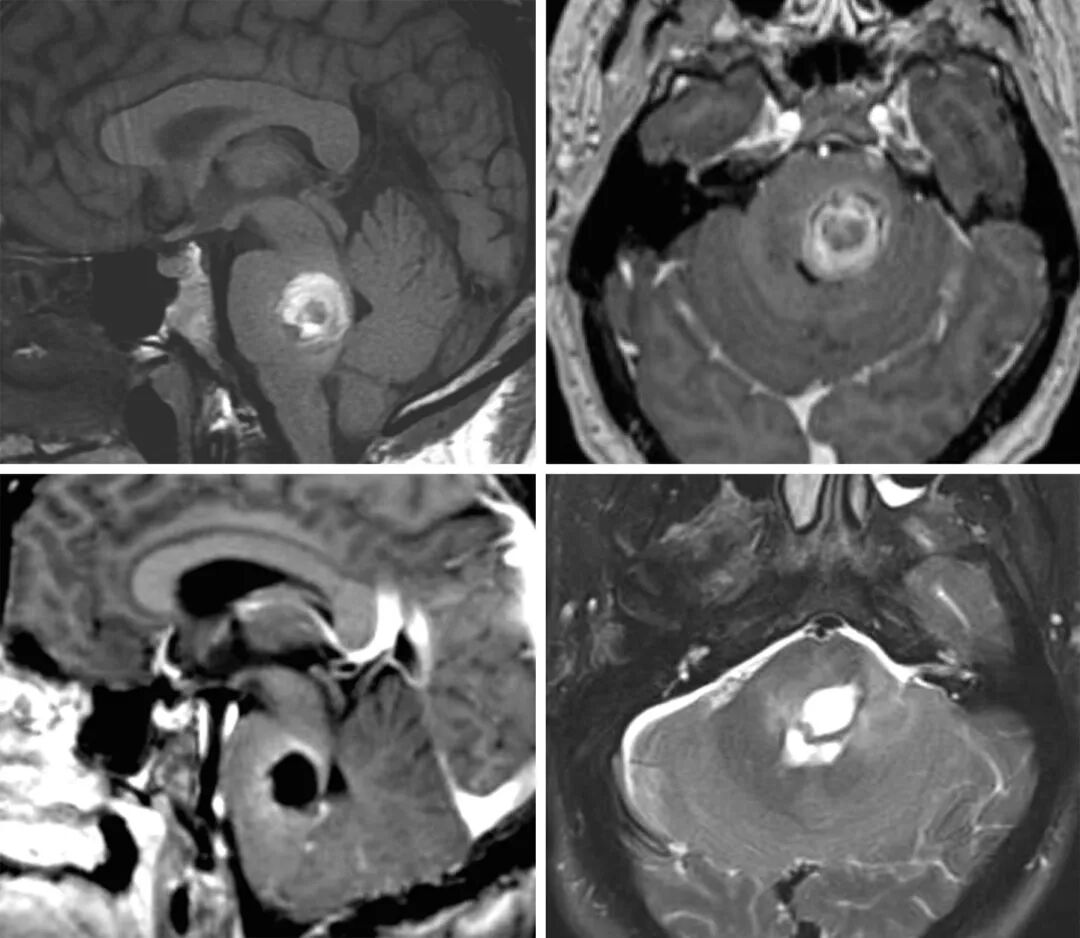

图1:图示一个桥脑后部的CM,合并明显的囊外出血(上排)。患者表现为急性轻偏瘫与颅神经功能障碍,最终行显微手术(下排)。切除的细节请参阅下面的插图。